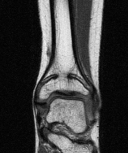

| SH I distal tibia / fibula | SH II distal tibia | SH III medial malleolus |

| Low risk growth arrest | 40% risk growth arrest | 30% risk physeal bar |